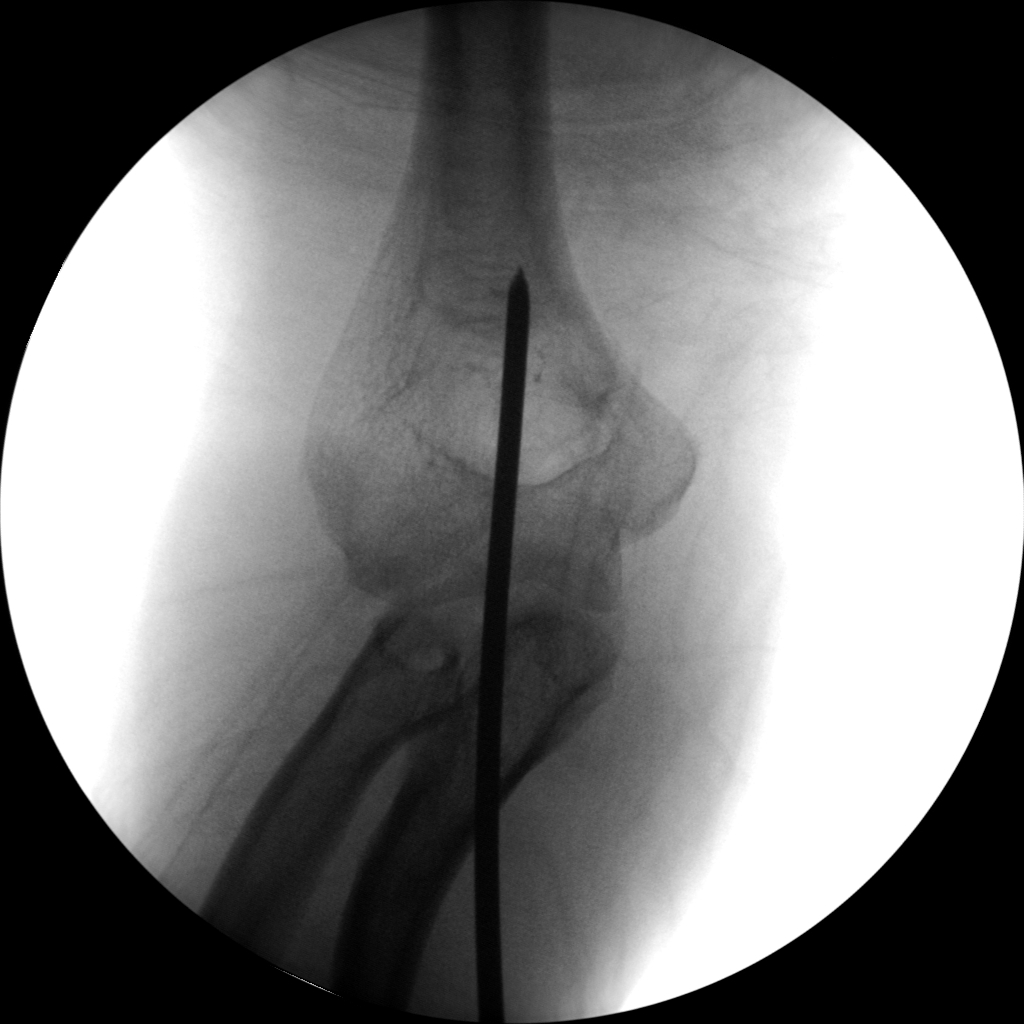

Skan-C plays a critical role in orthopaedic procedures, providing excellent imaging during interventional procedures, and allowing for precise localization and accurate treatment. The ability of Skan-C to offer dynamic visualization of visualization structures enhances patient safety, minimizes complications, and improves the overall effectiveness of orthopedic interventions.

Orthopedic procedures in which Skan-C is highly effective are

CRIF - Closed reduction internal fixation

ORIF - Open reduction internal fixation

High-quality imaging

Skan-C uses advanced imaging technology, such as pulsed fluoroscopy and digital subtraction angiography, to provide highly detailed images of the affected area. This allows doctors to perform procedures with increased precision and accuracy, and better patient outcome